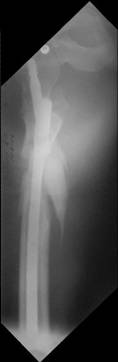

I would use a small wire distractor mentioned in the list some times. Proximal wire is in the iliac crest in AP direction. The leg is adducted. I attached some images. At the AP view under image intensifier you can see adduction but even slight valgus reduction.